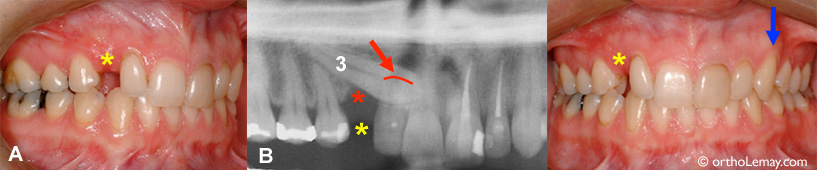

(A) Une femme de 26 ans avec une canine supérieure droite complètement formée, mais sévèrement incluse du côté du palais(B-3).

Cette condition, qui est en progression depuis au moins 15 ans, aurait possiblement pu être évitée avec une supervision adéquatependant l’éruption des dents (prise de radiographies et extractions sélectives).

Le fait d’avoir gardé la canine incluse pendant toutes ces années a eu plusieurs conséquences dommageables pour l’environnement de cette dent :

Avec les années, la canine temporaire est tombée lorsque la canine permanente incluse a progressivement usé sa racine. Il en résulte un espace important et inesthétique où était la canine temporaire (* jaune).

(B) La canine incluse a résorbé (usé) plus de 40% de la racine de l’incisive permanente latérale supérieure droite. La flèche et la ligne rouges indiquent le bout de la racine usée. La santé et survie de cette incisive latérale est maintenant incertaine à long terme.

Un défaut osseux très important (perte d’os visible en foncé sur la radiographie) s’est développé dans la région de la canine droite (* rouge) de sorte qu’une tentative de loger la canine dans l’arcade peut nécessiter une chirurgie pour ajouter de l’os ou être vouée à l’échec.

En comparaison, la canine gauche est descendue normalement par elle-même (flèche bleue).

Si un traitement d’orthodontie est envisagé, il serait à considérer d’extraire la canine incluse qui n’a pas assez d’os dans son environnement pour la descendre en place.